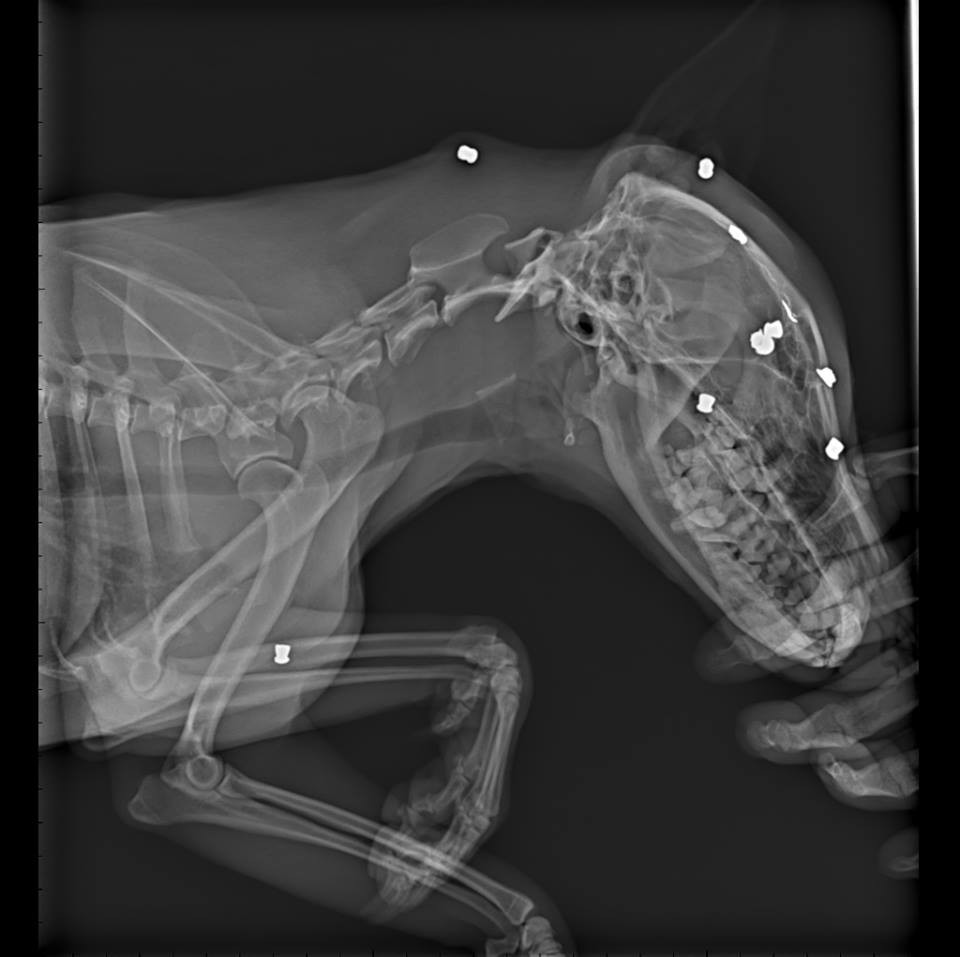

Našlo se celých 12 kulek. Vyndat ale šly pouze 3